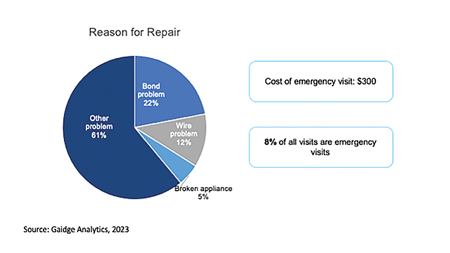

Abstract Orthodontic treatments can seem overwhelming, burdensome, and uncomfortable for patients, parents, and – when it comes to emergency visits – for orthodontists as well. As we evolve the industry, we must keep the patient’s experience top of mind and put them in the driver’s seat. In her article, Dr. Sima Yakoby Epstein, Founder and CEO of … Read more